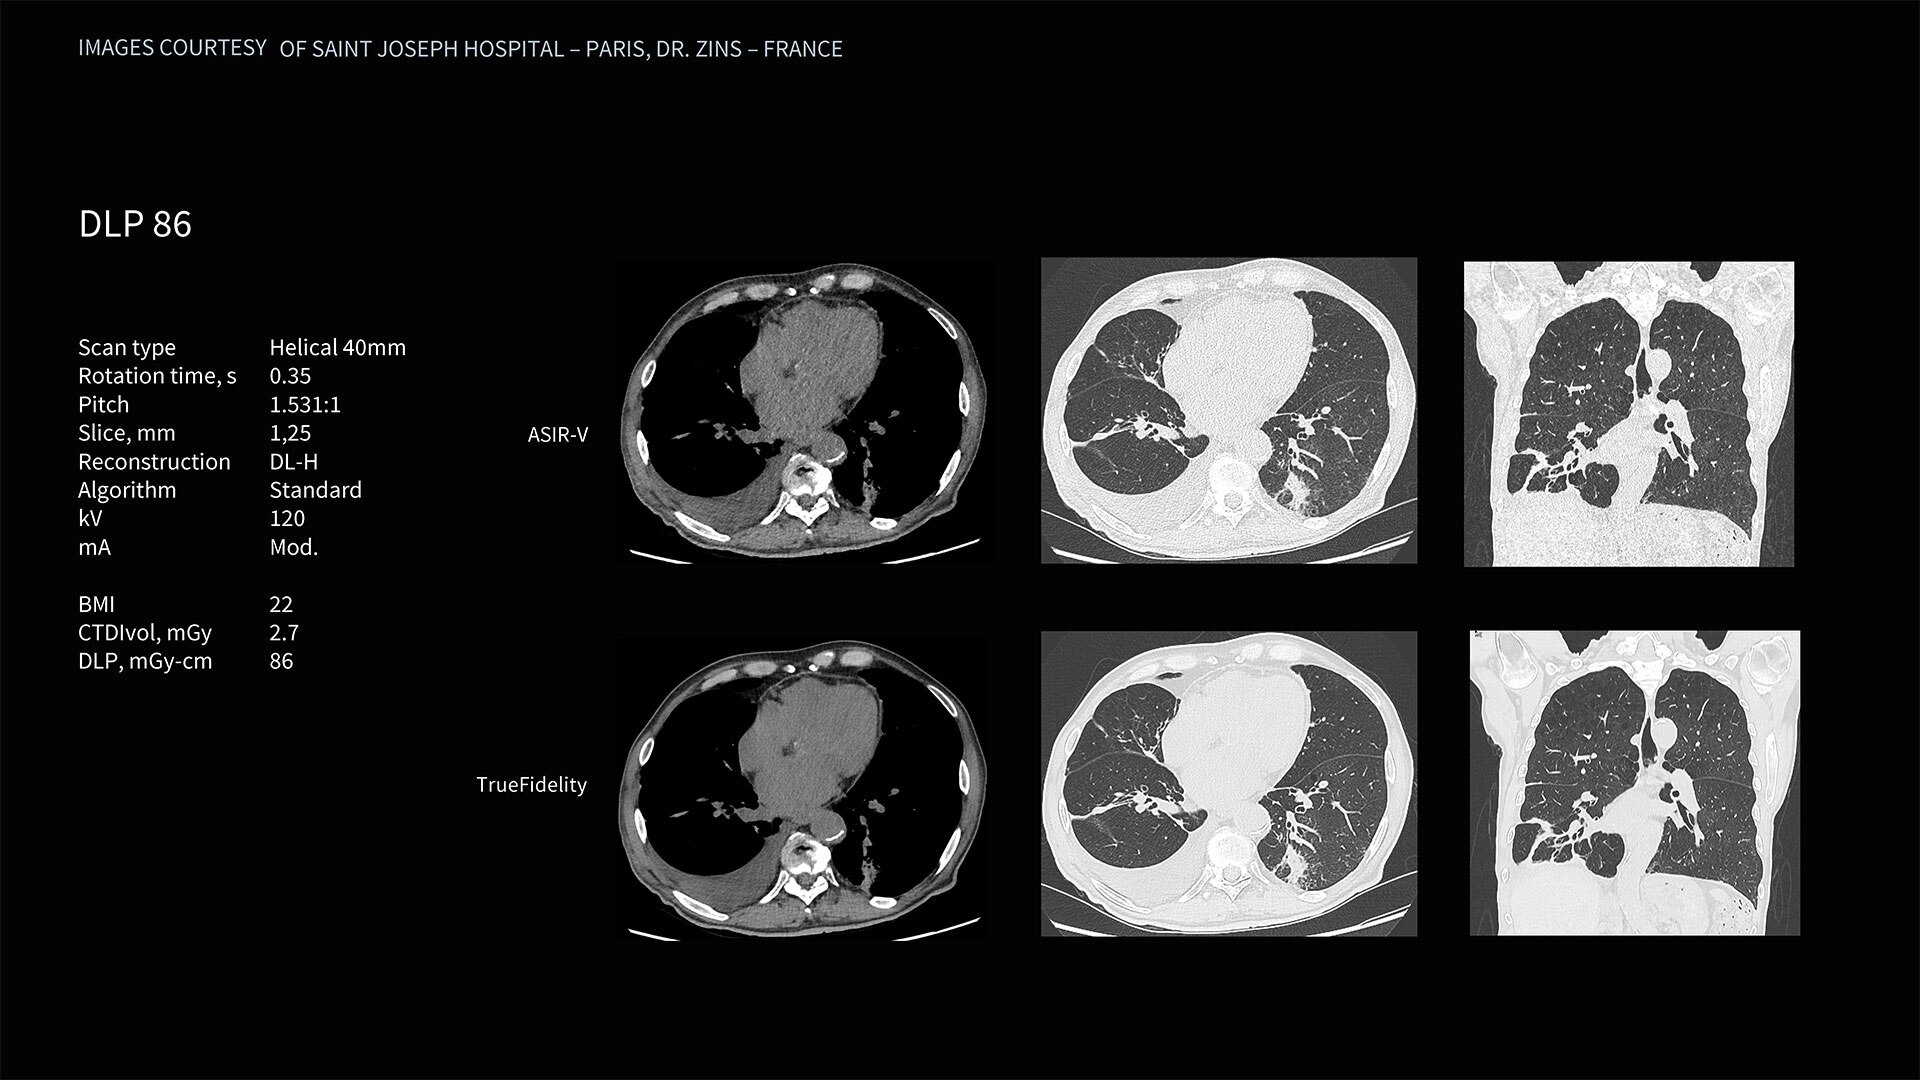

Deep learning image reconstruction, higher special resolution at 0.23 mm

Address individual clinical needs, moving seamlessly from one scan mode to the next. Image with a stunning 0.23 mm spatial resolution, then switch to rapid kV switching for full 50 cm FOV spectral imaging of the entire body. Choose up to six times reduction in motion artifact using SnapShot Freeze 2¹ for coronary artery CTA and reduce all-round dose with next-generation iterative reconstruction.